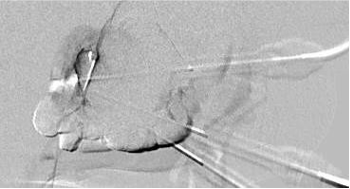

Carm CT 辅助引导 在超声或透视引导下进行的经皮泡沫硬化疗法,如今已被普遍认为是治疗静脉畸形(VM)的主要方法。但也有报道Carm CT成像方式在评估药物注射范围及硬化疗法终点方面的可行性。 CT(锥形束CT)作为注射终点的监测手段,与荧光透视法相比有何不同,在编写这个栏目时,这些报道多少有些主观的经验 静脉畸形 治疗 在超声引导下,使用 23 号针对静脉导管进行了穿刺。 在注射硬化剂之前,为了确认造影剂的分布情况,我们进行了数字减影血管造影(DSA)检查。如果造影剂分布不充分,就会再插入一根针。 用这些针头分别注入了泡沫聚多卡醇(浓度为 1% 或 3%,使用的是二氧化碳或室空气)。 影像评估: 注射完成后,进行CBCT检查,并将空气分布情况与之前的增强型对比增强 CT 或 MRI 结果进行了对比评估。 在空气分配不足的情况下,会在同一治疗过程中进行额外的注射。 终点 主要的评估指标是检验所有疗程中的额外注射剂量。 次要指标是评估总的辐射剂量,包括透视和锥形束计算机断层扫描(CBCT)的剂量,以及 CBCT 的辐射剂量。